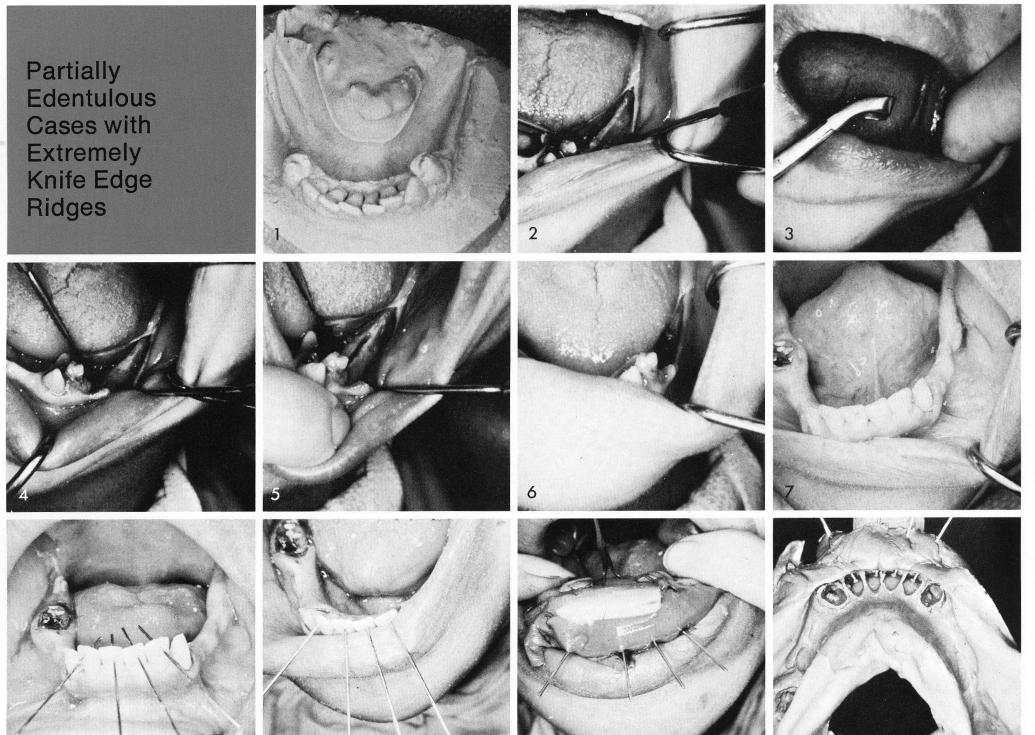

In an extremely knife edge ridge, figs. 1, 2, it is imperative that before a blade can be contemplated, it must be interpreted whether or not the occlusal table can be made wide enough to accept a groove, by reducing the fragile crestal bone. Either with a bone rongeur, fig. 3, round stone, or bur, or all three, the ridge is reduced and widened, fig. 4, and the groove is made, fig. 5, and the implant is accepted, fig. 6.

Fig. 7 shows a knife edge ridge on the left posterior quadrant. Holes were drilled horizontally above the pulp horns through the four incisor teeth and pins were placed through them, fig. 8. They were then backed up to fit flush with the lingual surfaces of the incisor teeth, fig. 9, to facilitate the impression technique, fig. 10, allowing the impression to be removed without tearing or distorting, fig. 11. The necessary lingual castings were fashioned to fit over the prepared lingual surfaces of the incisors and full crown coverage restorations were cast for the remaining cuspids and right molar, fig. 12.

1 Widening mandibular occlusal table by reducing fragile crest bone